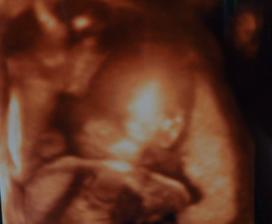

12.8.2010 - dneska jsem byla na 3D UTZ- malá se nechtěla fotit a pořád si strkala před obličejíček nožičky a ručičky, ale i tak to bylo úžasné